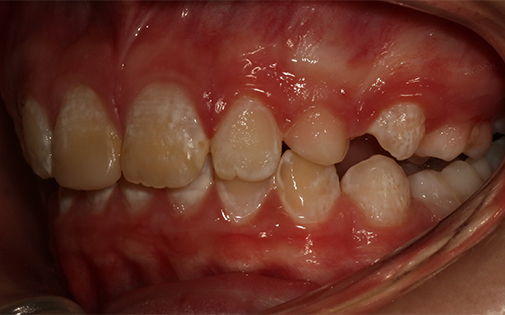

This patient presented with a very severe malocclusion (i.e. irregularity of her teeth and jaws). The ideal treatment recommended was removal of four teeth, upper and lower fixed braces and surgery to her jaws. However, the patient was not keen on the idea of surgery so she offered the alternative of removal of two upper teeth and Invisalign clear aligners. With the expertise of our specialist orthodontists, even the most challenging cases can be treated successfully with Invisalign.